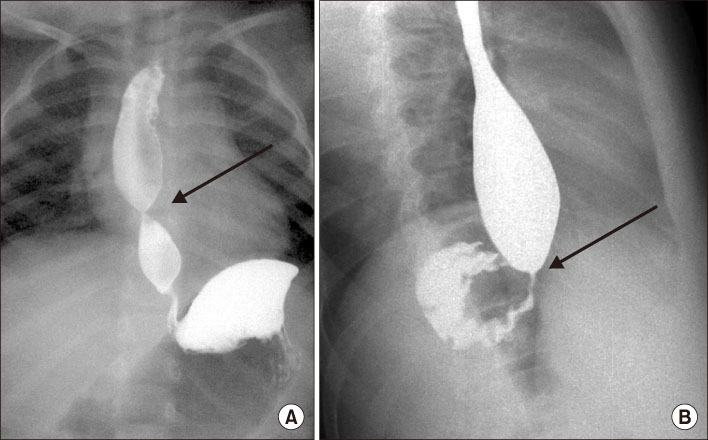

Fig. 3

Endoscopic ultrasound revealed hypoechoic structure in the esophageal wall. Data from the article of Quiros et al. (J Pediatr Gastroenterol Nutr 2013;56:e14) [18].

Fig. 3 Endoscopic ultrasound revealed hypoechoic structure in the esophageal wall. Data from the article of Quiros et al. (J Pediatr Gastroenterol Nutr 2013;56:e14) [18].